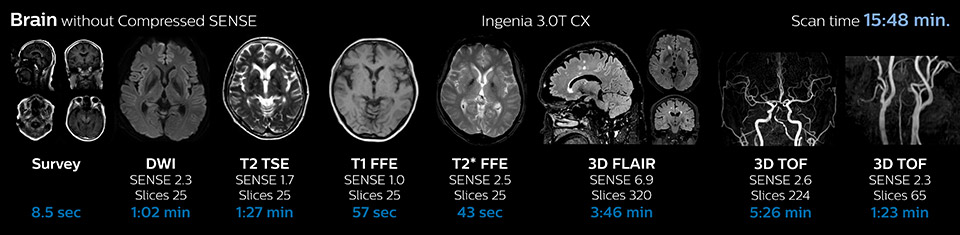

Reduction of scanning time with Compressed SENSE

| KNC ExamCard | Total scan time before | Total scan time with Compressed SENSE | Change |

| Brain | 15:48 min. | 10:19 min. | -35% |

The most frequently used brain MRI examination at KNC included approximately 15 minutes of scanning time, and was quite comprehensive with fairly short scan times. When Compressed SENSE became available, its great impact on the brain exam quickly became clear.

Scanning time reduction in brain MRI with Compressed SENSE

Fast MRI of brain

With Compressed SENSE, the scan time for the routine brain examination at KNC was reduced from 15:48 to 10:19 minutes, which corresponds to 35% reduction.

Ingenia 3.0T CX

Scan time 15:48 min.